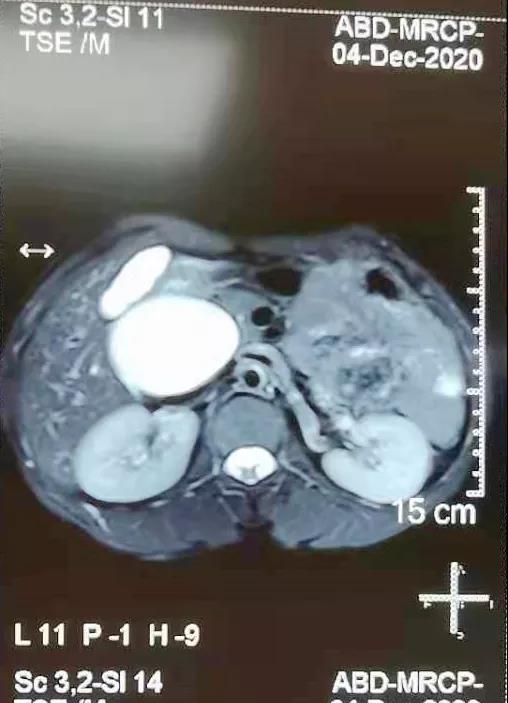

(▲术前MRCP影像资料)

患者女性,38岁,因“间歇性上腹部疼痛半年余”为主诉入住普外科。入院后,科室主任张永全立即召集全科医师对患者进行详细检查,并对病情进行了分析讨论,最终诊断为:胆总管囊肿(Ⅰ型)。手术指征明确,在得到患者及家属同意后,由张永全主任主刀,李金科副主任医师、韩云英主治医师、崔仁杰住院医师协助,在全麻下为患者行先天性胆总管囊肿切除胆道重建成形术,术中完全切除胆总管囊肿及开口于囊肿的胆囊,行肝总管空肠Roux-Y吻合术,并留置胆道支架管,手术过程顺利,患者术后安返病房,恢复良好。